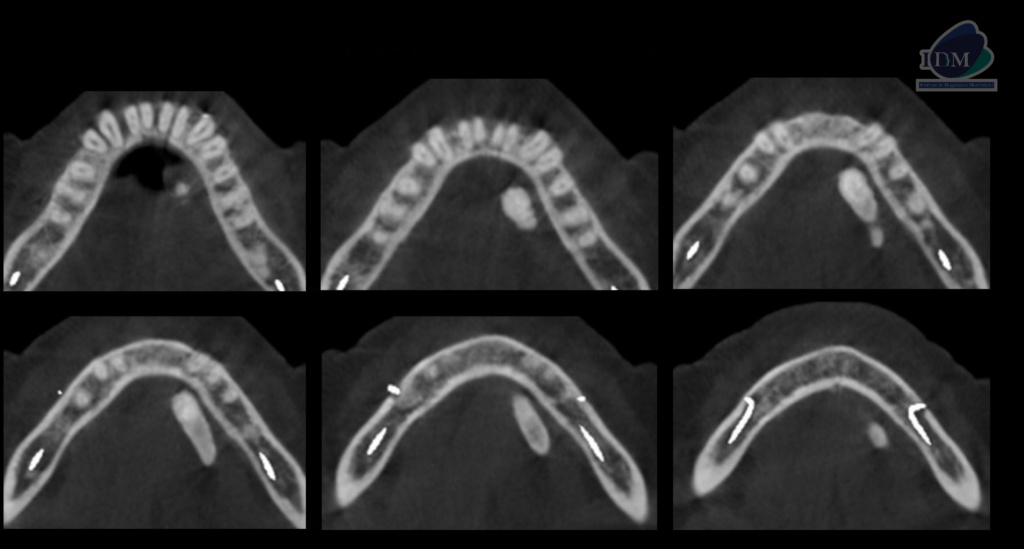

A la evaluación de la tomografía computarizada cone beam en cortes axiales, coronales y transaxiales se observa una imagen hiperdensa con una pequeña área hipodensa central que se localiza por lingual de aproximadamente 20 mm, a nivel del tercio apical de la pieza 33 hasta la raíz distal de la pieza 36. En la reconstrucción en 3D se puede observar de manera más didáctica la relación con las estructuras adyacentes y la forma que presenta, signos imagenológicos compatible con sialolito submandibular.

CORTES AXIALES